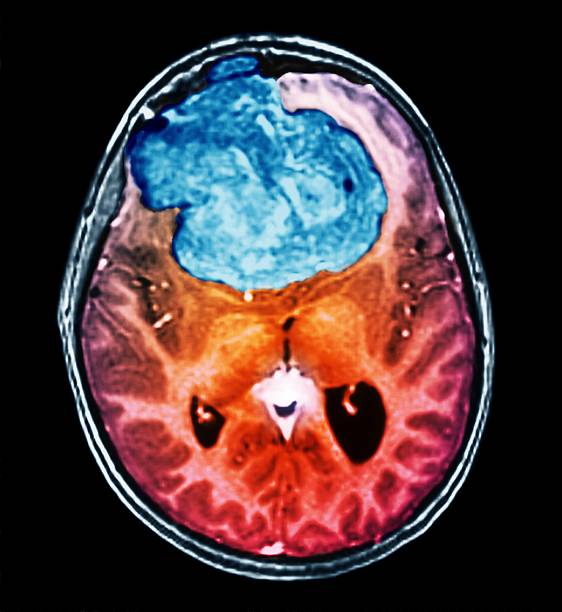

A deep learning application using YOLO and Grad-CAM to detect and visualize brain tumors from MRI images with explainable AI insights.

View on GitHub View on Streamlit